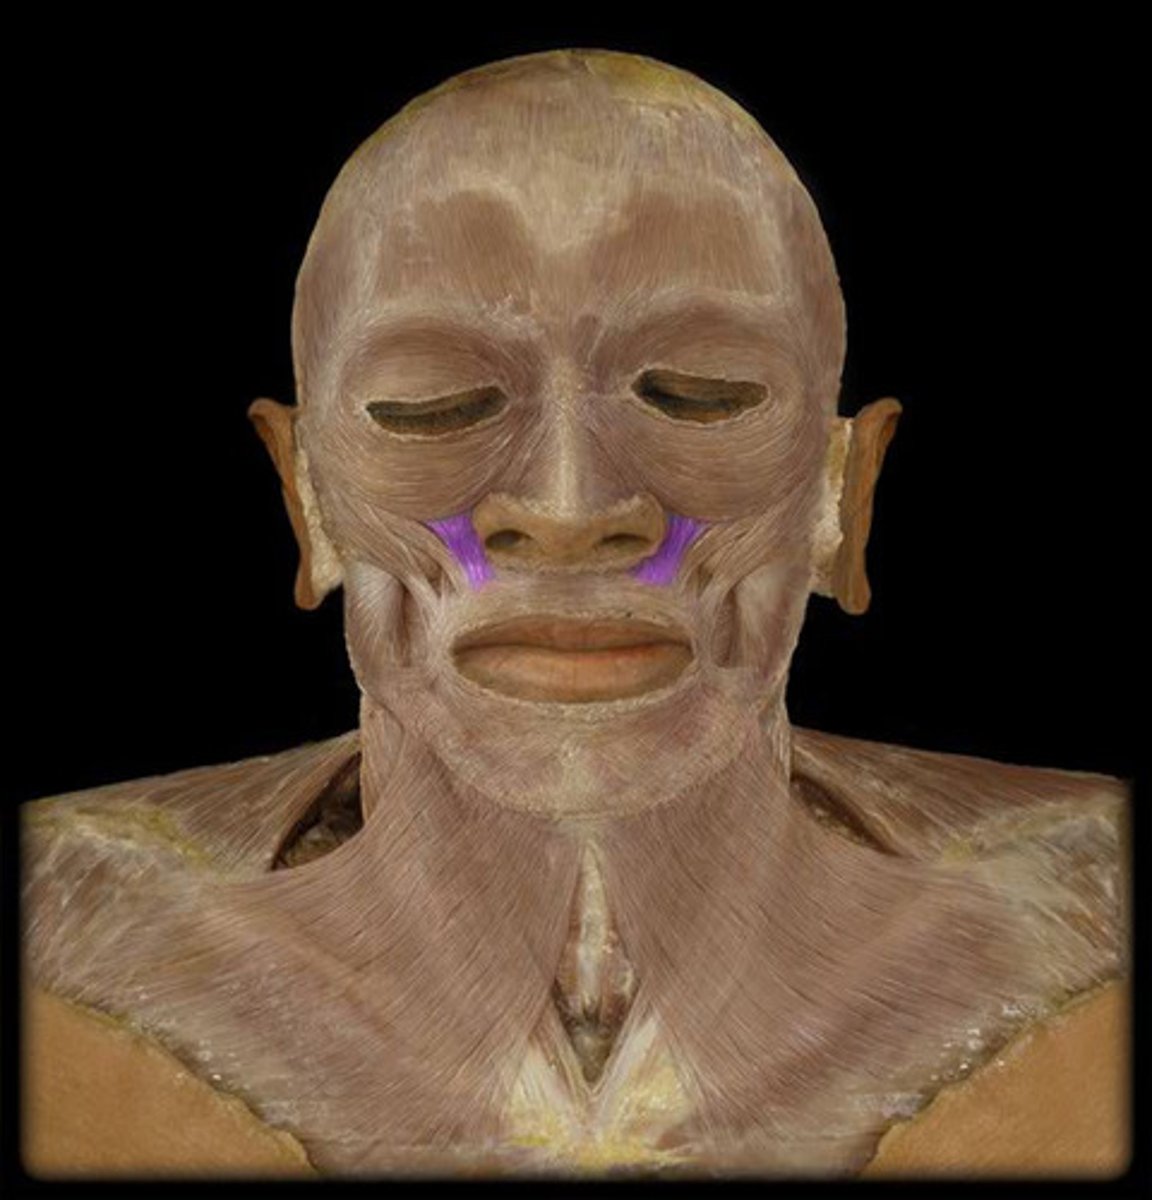

Nasalis m.

Origin: maxilla

Insertion: Nasal Cartilage

Action: Compress nares

Levator labii superioris m.

Origin: maxilla

Insertion: superior lip

Action: elevate